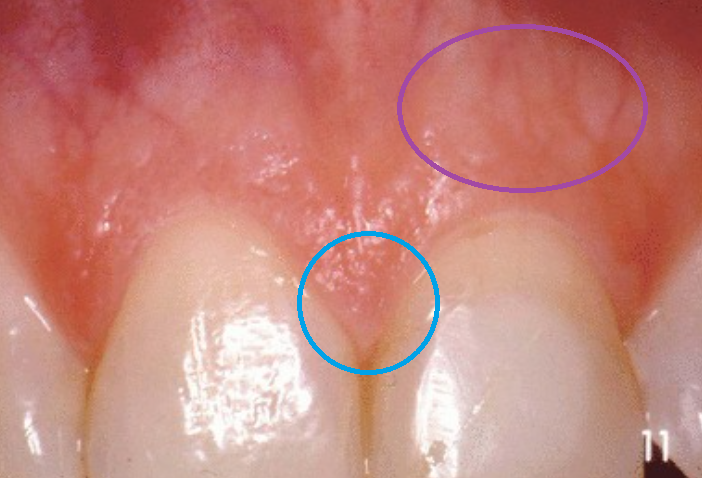

Anatomical areas of the gingiva are missing when you see open spaces apical to the contact areas

interdental gingiva

interdental col

valley-like depression in the portion of the interdental gingiva that lies directly apical to the contact area of 2 adjacent teeth and contacts the facial and lingual papillae

absent if adjacent teeth are not in contact